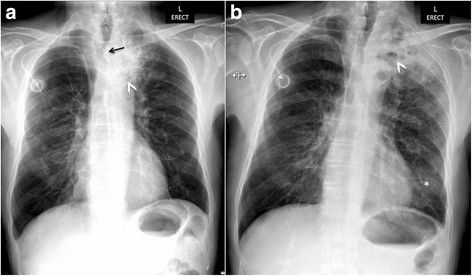

На фоне проводимой лучевой терапии отмечено ухудшение состояния с нарастанием одышки. При рентгенографии органов грудной клетки диагностирована пневмония (рис. 2 — а), которая не регрессировала на фоне проводимой антибактериальной терапии (рис. 2 — b).

Рисунок 2 [1].